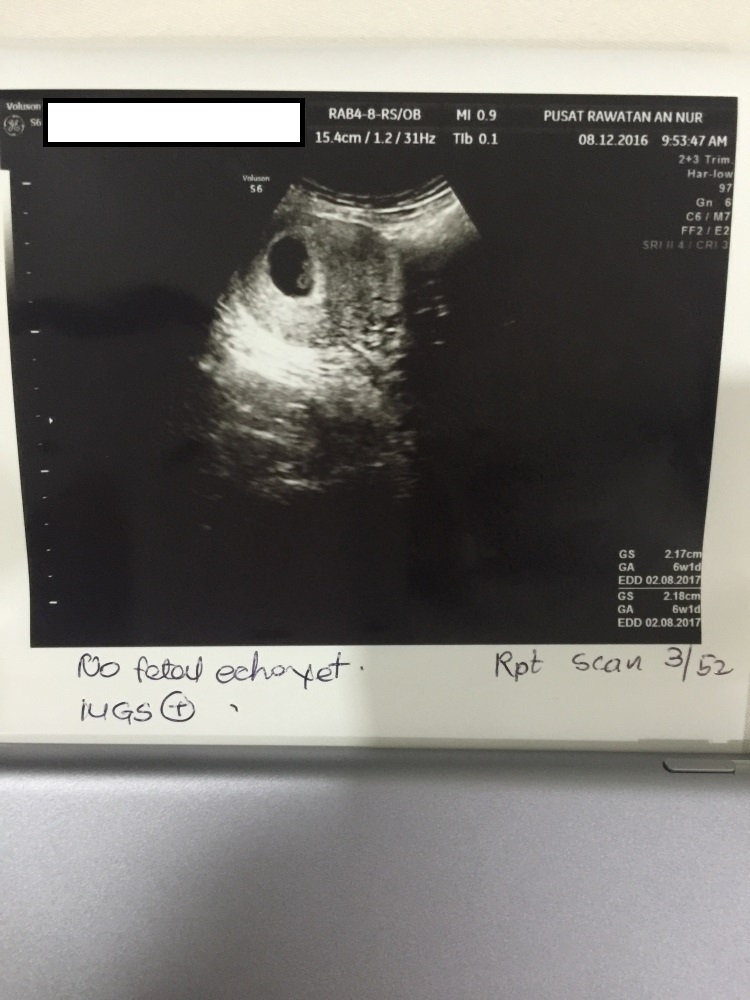

- Scan dibuat pada awalnya di Poliklinik Wahidah pada 1 December

- Kemudian buat lagi scan di Pusat Rawatan An Nur pada minggu berikutnya

Minggu ke – 6

Minggu ke-6